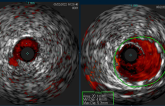

• OCT (11)

• (-) IVUS/NIRS (17)

OCT, IVUS Both Seem to Be Good Options for Complex Coronary Lesions

Optical Coherence Tomography-Guided or Intravascular Ultrasound-Guided PCI: The OCTIVUS Randomized Clinical Trial